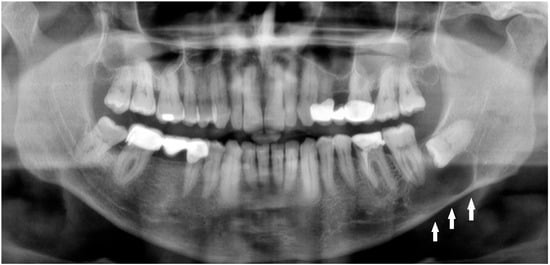

Figure 1. Radiolucent lesions of the mandible often remain unnoticed for years, silently expanding within the bone without any symptoms or visible changes [1]. In certain cases, these deceptively quiescent lesions may weaken the mandibular structure over time and predispose it to unexpected fractures, even after minor trauma [2]. Such an incidental and asymptomatic presentation was observed in the following case. A 50-year-old male patient was referred by a local radiologist following a routine dental panoramic radiograph (DPG) that revealed an incidental finding (Figure 1, white arrows shows the inferior border of the lesion). The patient was systemically healthy, with no history of endocrine disorders such as primary or secondary hyperparathyroidism; metabolic bone diseases such as Paget’s disease; or systemic conditions affecting bone metabolism, including renal osteodystrophy secondary to chronic renal failure, all of which can produce radiolucent lesions in the jaws. Clinically, the patient was asymptomatic, exhibiting no pain, swelling, abscess formation, or facial asymmetry, and no cortical expansion was detected on examination. Radiographic assessment demonstrated that the right mandibular third molar was fully erupted, whereas the left mandibular third molar was completely impacted and retained within the bone. A well-defined, corticated, unilocular pericoronal radiolucency enveloping the crown of the impacted tooth was observed, extending from the enamel–cementum junction, radiographically consistent with a dentigerous cyst. Cone-beam computed tomography (CBCT) confirmed a unilocular lesion with marked buccolingual expansion and cortical thinning in the left posterior mandible but without obvious cortical interruption or a clearly visible fracture line, and the inferior alveolar canal remained corticated and mildly displaced. Nevertheless, because clinical and radiographic findings alone are insufficient for a definitive diagnosis, histopathological evaluation was deemed necessary to confirm the nature of the lesion. Quite often, the extent of a bone lesion may be underestimated, which can lead to an iatrogenic fracture during the removal of a cyst or an impacted tooth. Additionally, a pathological mandibular fracture may occur shortly after surgery. In the present case, the lesion was treated by cyst enucleation and removal of the impacted third molar without prophylactic mandibular plating, as intraoperative mandibular stability appeared satisfactory and no crack propagation or bone bending was palpated. However, in the third postoperative week, the patient developed new-onset pain in the left mandibular region without any reported trauma, and repeat imaging revealed a non-displaced vertical fracture line extending from the distal aspect of the second molar toward the inferior border of the mandible, which was managed conservatively with intermaxillary fixation and close radiological follow-up. In such cases, several considerations should be made: improving diagnostics with CBCT; performing simultaneous preventive or prophylactic mandibular plating (PMP); using other maxillomandibular fixation devices to enhance bone stability, prevent fracture, and promote proper healing; or combining PMP with bone grafting after cyst or tooth removal to significantly reduce the likelihood of mandibular fracture [1,2,3,4]. Three-dimensional assessment of bone condition is fully achievable with CBCT, while the extent of bone loss in the mandible and the size of the three-wall bone defect might influence the use of any bone graft material with or without a PMP. On the other hand, those situations are case-dependent and vary greatly among patients. Secondly, when a standard DPG is used for fracture assessment, whether after typical trauma or following the removal of a large cyst, tumor, or impacted molar, the presence of minimally displaced fracture patterns, very narrow fracture lines, or inconclusive bone findings may lead to failure in identifying a fracture.